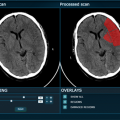

The £1.25 million University of Oxford Isis Fund has made its first investments in medical device spin-out Oxtex and in Brainomix. -